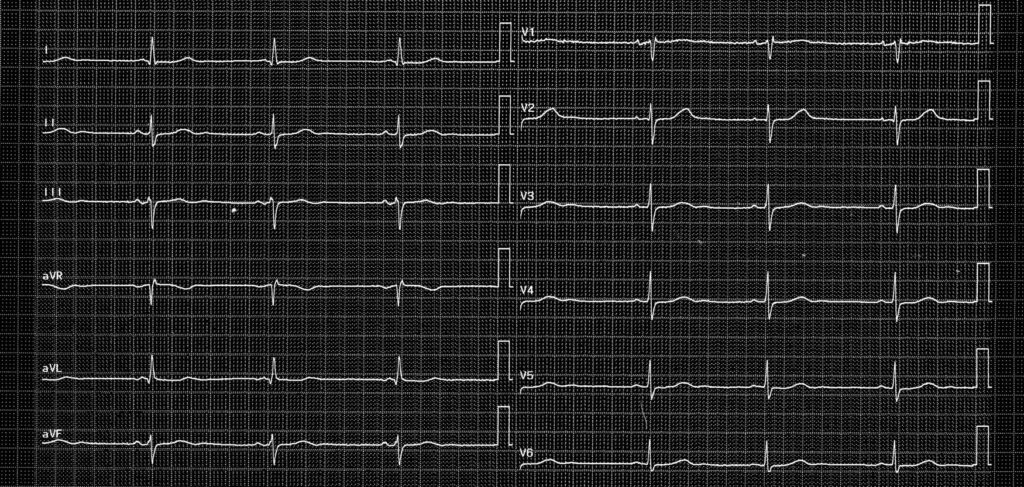

Tracé 2.1: Bradycardie sinusale

Homme de 64 ans, hypertendu traité par amlodipine; électrocardiogramme de surface de contrôle; patient asymptomatique

Activité atriale sinusale (ondes P positives en DI, DII, V5, V6 et négatives en aVR); bradycardie sinusale avec fréquence à 45 bpm, PR normal, QRS fin;

Ce patiente présente une bradycardie sinusale correspondant à une fréquence cardiaque inférieure à 50 ou 60 bpm (en fonction des définitions) au repos. La différence entre bradycardie physiologique et pathologique est parfois difficile à déterminer. En effet, une hypertonie vagale fréquemment observée chez les patients sportifs peut expliquer une bradycardie physiologique sans nécessité d’investigations particulières ou de traitement. Une étiologie médicamenteuse est également fréquemment observée (bétabloquant, digoxine, amiodarone, inhibiteur calcique…). Le caractère pathologique et la sanction thérapeutique (implantation d’un stimulateur) sont donc déterminés par l’existence de symptômes qui sont indispensables mais peuvent être plus ou moins sévères et plus ou moins spécifiques (syncopes, lipothymies, asthénie, vertiges). Une insuffisance chronotrope (définie par l’incapacité à atteindre une fréquence cardiaque à l’effort supérieure à 70, 80 ou 85% de la fréquence maximale théorique en fonction des définitions) peut s’accompagner de symptômes n’apparaissant qu’à l’effort (limitations des capacités d’effort, dyspnée d’effort).

Il a été décidé de ne pas implanter ce patient asymptomatique présentant une fonction chronotrope préservée (accélération normale de la fréquence cardiaque à l’effort) mais de le surveiller avec la réalisation régulière d’enregistrements Holter- ECG à la recherche de bradycardies paroxystiques plus marquées. Un traitement par bétabloquant ou par inhibiteur calcique bradycardisant est à déconseiller pour son hypertension.

L’existence d’une bradycardie sinusale modérée n’est pas pathologique en soit. L’implantation d’un stimulateur ne se justifie qu’en présence de symptômes.